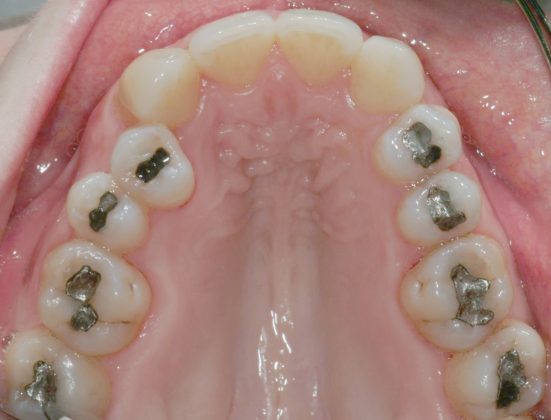

Il protocollo terapeutico ha previsto l’estrazione del primo premolare inferiore sinistro (3.4) e del primo superiore destro (1.4), l’applicazione di una apparecchiatura fissa linguale 2D e di una meccanica asimmetrica di ancoraggio e movimento ortodontico a entrambe le arcate (Figure 3a-b).

Il trattamento è iniziato con l’estrazione dei due premolari in unica seduta in anestesia locale e l’applicazione simultanea, dopo una settimana, della apparecchiatura linguale inferiore e superiore, non essendoci problemi di overbite e potenziali interferenze in occlusione tra l’apparecchiatura superiore e i frontali inferiori. All’arcata superiore è stata effettuata una iniziale chiusura dello spazio estrattivo con forze molto leggere in ancoraggio medio su arco .014” Nichel-Titanio e successivamente .016” Nichel-Titanio, bondato in prima fase per maggior stabilità direttamente sulla superficie mesiale di 2.4.

Nota tecnica: il movimento iniziale di distalizzazione della corona di 1.3 mediante tipping distale (vista la posizione radicolare iniziale) è stato ottenuto con una catenella elastica leggera inserita su 1.6, 1.5 e ancorata su 1.3, abbracciando per maggior controllo l’aletta disto-occlusale e quella gengivale del bracket linguale.